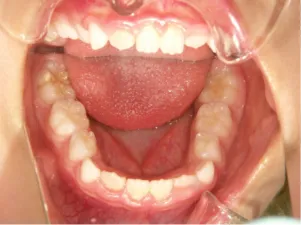

治療前①小1(7y2m):初診

*上顎前歯後方傾斜、上下唇の突出、口唇閉鎖不全傾向、コンケーブなし

| カウンセリング・診断結果 | 骨格的に下顎前方位で下顎骨も大きいタイプで、上の前歯が後ろに傾斜している受け口です。 顔立ちは上下唇が突出していて口唇閉鎖不全傾向がありますが、コンケーブにはなっていません(写真①)。 機能的に低位舌があり、今後受け口を助長する可能性があります。 受け口は、上顎骨の骨格的な前方向の成長を阻害し下顎が前へ強く成長していくため、骨格的な受け口が悪化し永久歯の咬合治療が難しくなり、症例によっては外科的な治療が必要になることがあるため早期に改善し骨格的な悪化を予防する説明をしました。 |